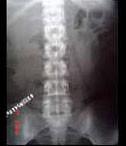

问题 女,28岁,持续性腰痛加重2天,伴尿频、尿急、尿痛及发热,MRI如图所示,下列说法正确的是 ( )

选项 A、考虑为输尿管癌所致的梗阻积水 B、考虑为输尿管囊肿 C、考虑为先天性巨输尿管 D、考虑为输尿管下端结石并积水 E、单侧输尿管明显扩张,同侧的肾盂肾盏也扩张,但其程度轻于前者

答案 CE